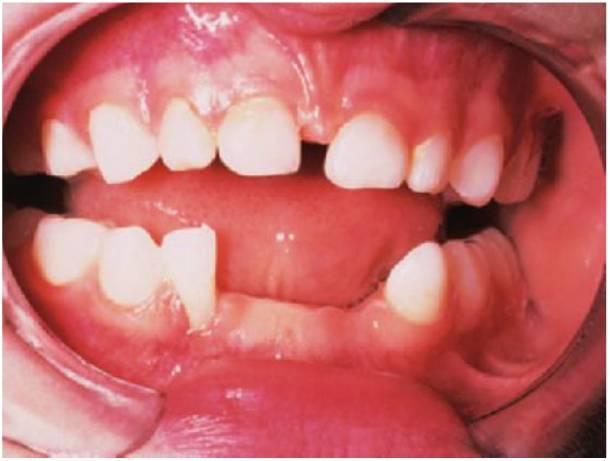

Ulceración de Riga-Fedé

Es una ulceración de la superficie ventral de la lengua causada por un traumatismo producido por los movimientos protrusivos y retrusivos continuos sobre los incisivos inferiores (fig. 8.5B). Se consideraba un hallazgo común en los casos de tos ferina; en la actualidad, se suele ver tan sólo en niños con parálisis cerebral.

Tratamiento

Pulir los bordes incisales agudos o colocar recubrimientos de resina composite sobre los dientes. En raras ocasiones se considerará la extracción de los dientes.